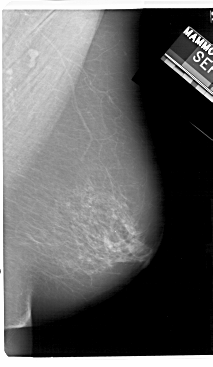

A_1181_1.LEFT_MLO

LEFT_MLO LINES 5491 PIXELS_PER_LINE 3406 BITS_PER_PIXEL 12 RESOLUTION 43.5 OVERLAY